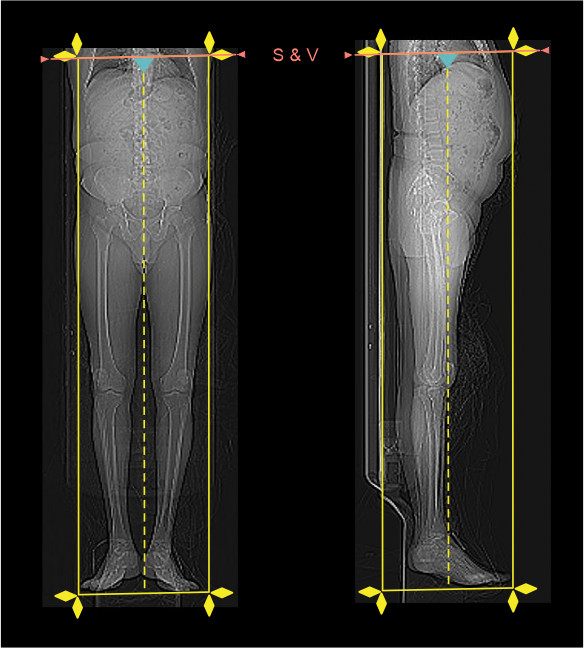

- Plan the scan slab to cover from diaphragm to ends of lower limbs (toes).

- Keep scan and view (S & V) slice just above diaphragm.